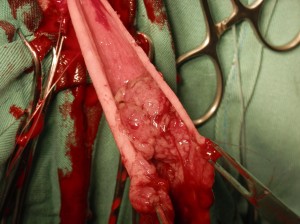

手術法:直腸粘膜プルスルー法

主訴:近隣の動物病院からのご紹介症例で、2週前から排便ポーズをとっても便がでない状態になり、直腸検査にて直腸に腫瘤が触知されため当病院に受診されました。レントゲン検査、大腸内視鏡検査にて、直腸領域に多発性の腫瘍が認められました。

肛門側からアプローチしまして、腫瘍が完全に見られない所で切除しました。